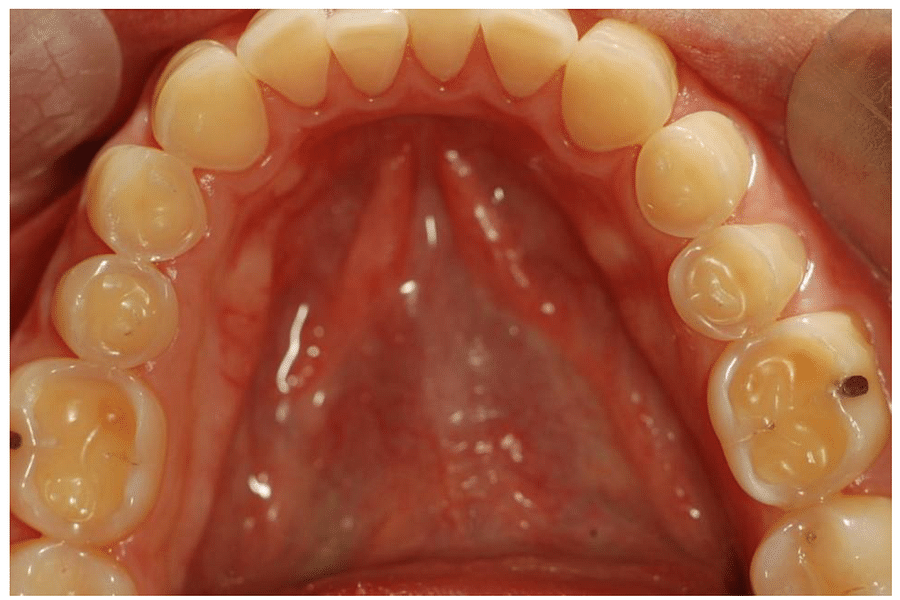

Utilizing Visual Aids for Patient Education

Visual aids are not just supplementary tools; they are crucial elements in bridging the communication gap between dentists and patients. By using diagrams, models, and digital presentations, we can demystify complex dental procedures and conditions. For instance, a 3D model of the teeth can help patients understand the intricacies of root canal therapy or the importance of proper alignment for oral health.

Moreover, incorporating visual content like informative videos can significantly enhance patient comprehension. Videos that depict proper brushing and flossing techniques or the progression of gum disease can be both captivating and educational. This dynamic approach to patient education not only informs but also engages patients in their own oral health journey.